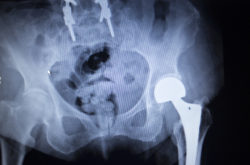

metal hip implantDePuy Orthopaedics is facing a new DePuy Pinnacle lawsuit from a Rhode Island couple who are filing their claim in a growing multidistrict litigation (MDL) against the company.  Their DePuy Pinnacle lawsuit is joining a group of similar claims, each alleging serious metal hip implant injuries were caused by the allegedly defective nature of the device.

Patricia underwent revision surgery on April 13, 2017, in which it was discovered that metal debris was found throughout the device’s acetabular cup as well as significant corrosion. She was diagnosed with blood metal poisoning (metallosis) and device failure, which ultimately forced her to undergo the revision surgery described in her DePuy Pinnacle lawsuit.

Metal hip implants can cause this with the interaction of the device’s ball and socket joints interacting. This can cause the metal hip components to corrode or fret, along with giving way for the formation of pseudotumors. These metal hip implant complications often force patients to undergo revision surgery.